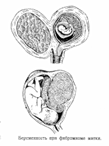

6? опухоль матки (миома матки: узел может расти

в сторону брюшной полости или в полость матки)

Миома больших размеров (10 недель и больше) – противопоказание

к вынашиванию.